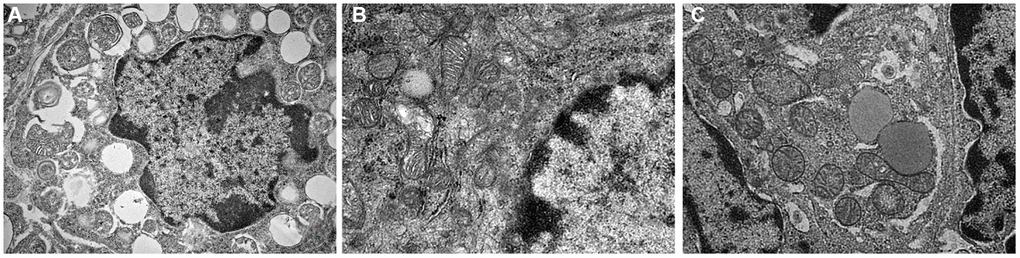

It was observed by electron microscope that the mitochondria were mostly long and the average volume increased, the density decreased, the number decreased number of mitochondria was reduced, and the lesions such as swelling, vacuolar degeneration and inclusion body formation appeared. Compared with the non-intervention group, the mitochondria of the aging intervention group were basically round, the distribution density was moderate, and the inner ridge was clear (Figure 5). The expression of mitochondria in the aging group was scattered in the concentrated distribution point. Compared with the non-intervention group, the mitochondrial distribution in the aging intervention group was more uniform (Figure 6). Membrane potential decreased in aging group (P = 0.0002). Compared with the non-intervention group, the aging intervention group was higher (Figure 7, Table 6).

Figure 5. Mitochondrial morphology under electron microscope. (A) Normal group; (B) Natural aging non-intervention group; (C) Natural aging intervention group (X5000).

Based on this, we found that the fluorescence intensity of oocyte mitochondria in aging group was lower than that in blank group, and the mitochondrial distribution of Yulinzhu intervention group was more uniform. Morphologically, oocyte maturation process was accompanied by changes in mitochondrial distribution, and lack of mitochondrial redistribution was sign of insufficient cytoplasmic maturation [17]. The mitochondrial morphology was further observed by electron microscope. After intervention, the mitochondria in the aging group were basically restored to circle, swelling and vacuolar changes almost disappeared, and the inner ridge was clear, indicating that the recovery of mitochondrial structure was very important to slow down aging. Mitochondrial membrane potential is a sensitive indicator of mitochondrial damage, reflecting the functional metabolism of mitochondria. Finally, the mitochondrial membrane potential was detected and compared with the normal group, the membrane potential of the aging non-intervention group decreased. Compared with the non-intervention group, Yu Linzhu intervention group increased.